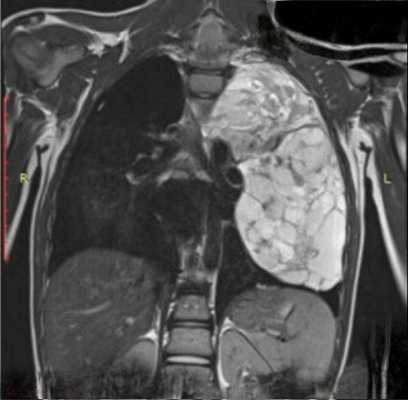

Аксиальный срез. Томограмма на уровне бифуркации трахеи. В переднем средостении достаточно большое патологическое образование, исходящее из вилочковой железы перед восходящей аортой. Это образование не выявляется на обзорных снимках, потому что в прямой проекции контуры средостения определяются анатомическими структурами или патологическими образованиями, которые кондурируются воздухсодержащей легочной тканью. Являются краеобразующими в этом случае.

В этой ситуации верхняя полая вена справа и нисходящая аорта слева формируют контуры средостения. Увидеть такое образование на рентгеновском снимке очень сложно, практически невозможно. Если у этого пациента миастения, то это и есть прямое показание к выполнению компьютерной томографии.

Томографическая картина. Мягкотканой плотности образования. В этом случае однородной структуры, овальной формы, с четкими контурами, расположенными перед восходящей аортой и общим стволом легочной артерии. Типичная характерная картина тимомы, которая, во-первых, нуждается в верификации, во-вторых, в соответствующем хирургическом лечении.

В этом случае, продолжая патологию вилочковой железы, огромные размеры карциноидной опухоли вилочковой железы, которые занимают все переднее средостение, оттесняя сердце и крупные сосуды сзади аорты, вызывают накопление жидкости в правой плевральной полости. Это огромная неоднородная структура патологического образования с гиперваскулярными участками, со сдавлением верхней полой вены.